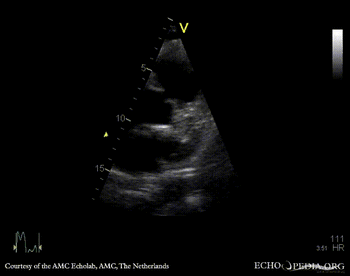

| Courtesy of: AMC Echolab, AMC, The Netherlands | |

| Suprasternal view | Suprasternal view |